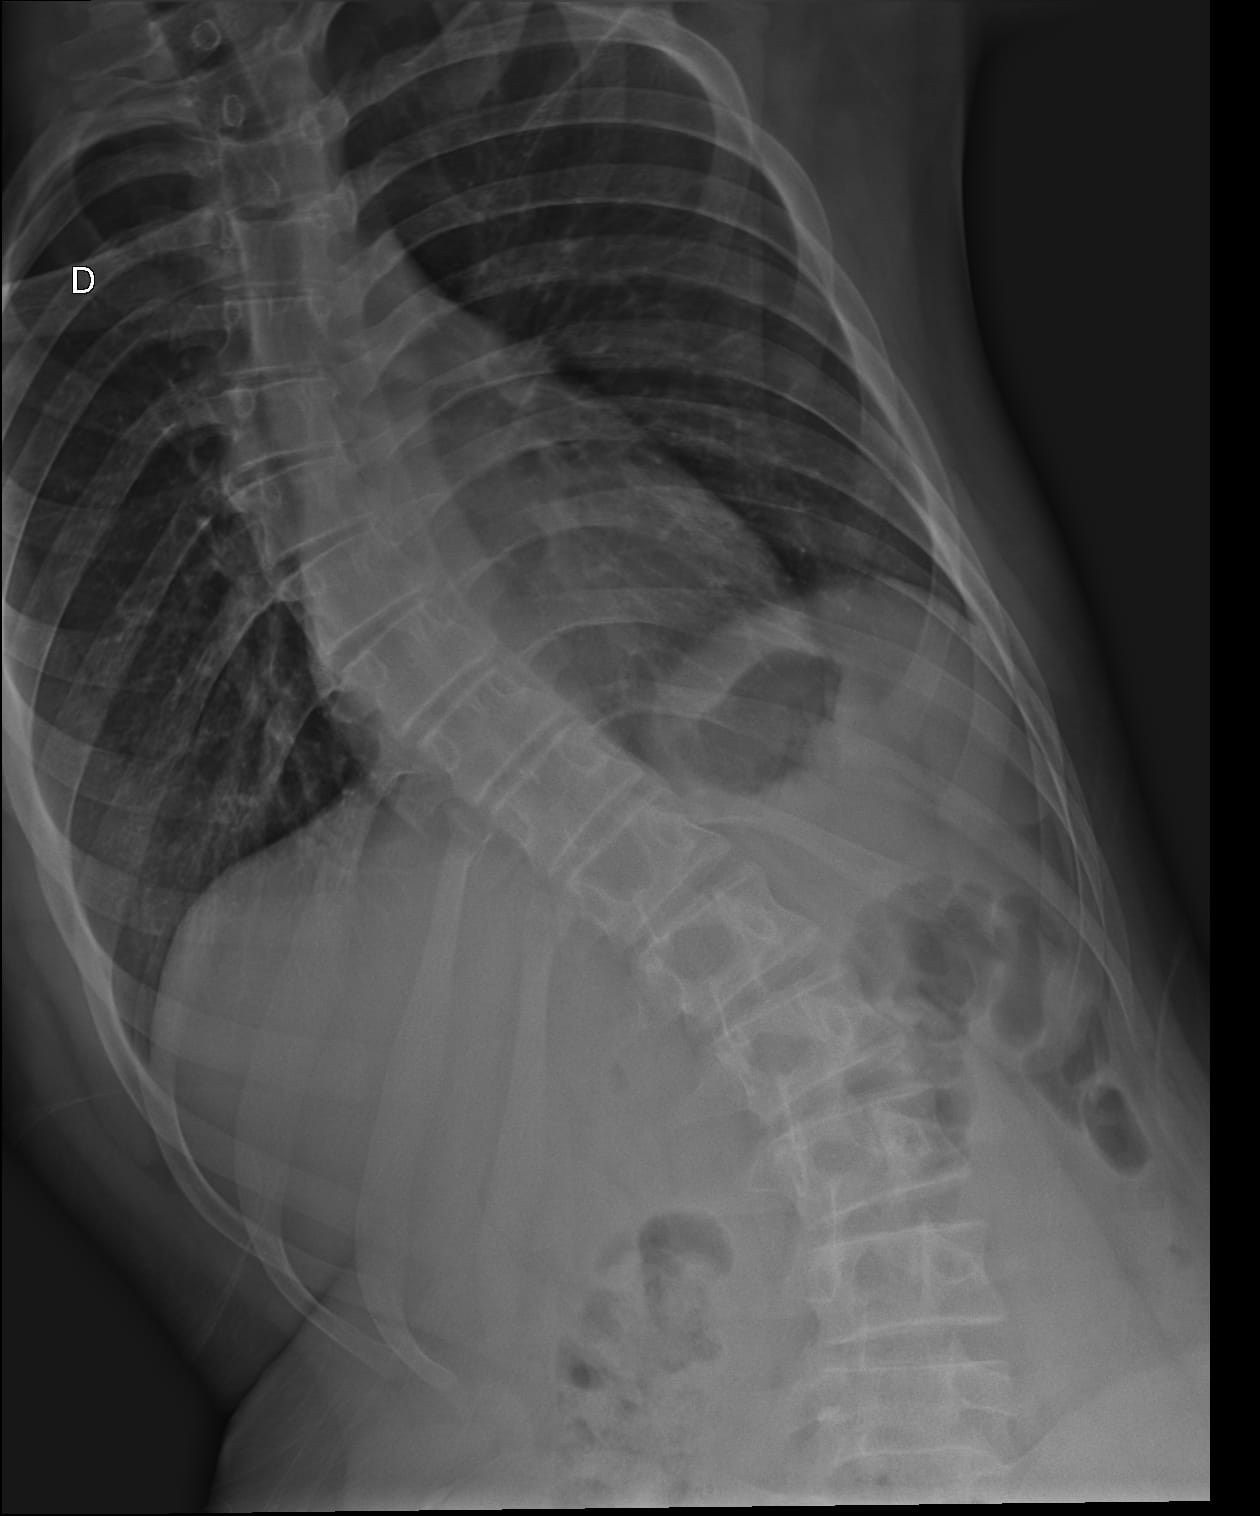

Matheus tem escoliose em grau avançado (curvatura em S de 42 graus), o que tem afetado profundamente sua qualidade de vida. Estamos em uma verdadeira batalha por exames e atendimentos médicos, muitos deles em outras cidades, o que gera gastos com transporte e alimentação que hoje não consigo cobrir.

Além da escoliose, Matheus também precisa de acompanhamento com neuropsicólogo e sofre de asma respiratória, o que exige cuidados constantes. No momento, estamos aguardando uma tomografia da coluna, exame essencial para avaliar a necessidade de cirurgia, conforme já indicado pelo médico. Também preciso providenciar óculos novos para ele, mas infelizmente estou sem condições financeiras.